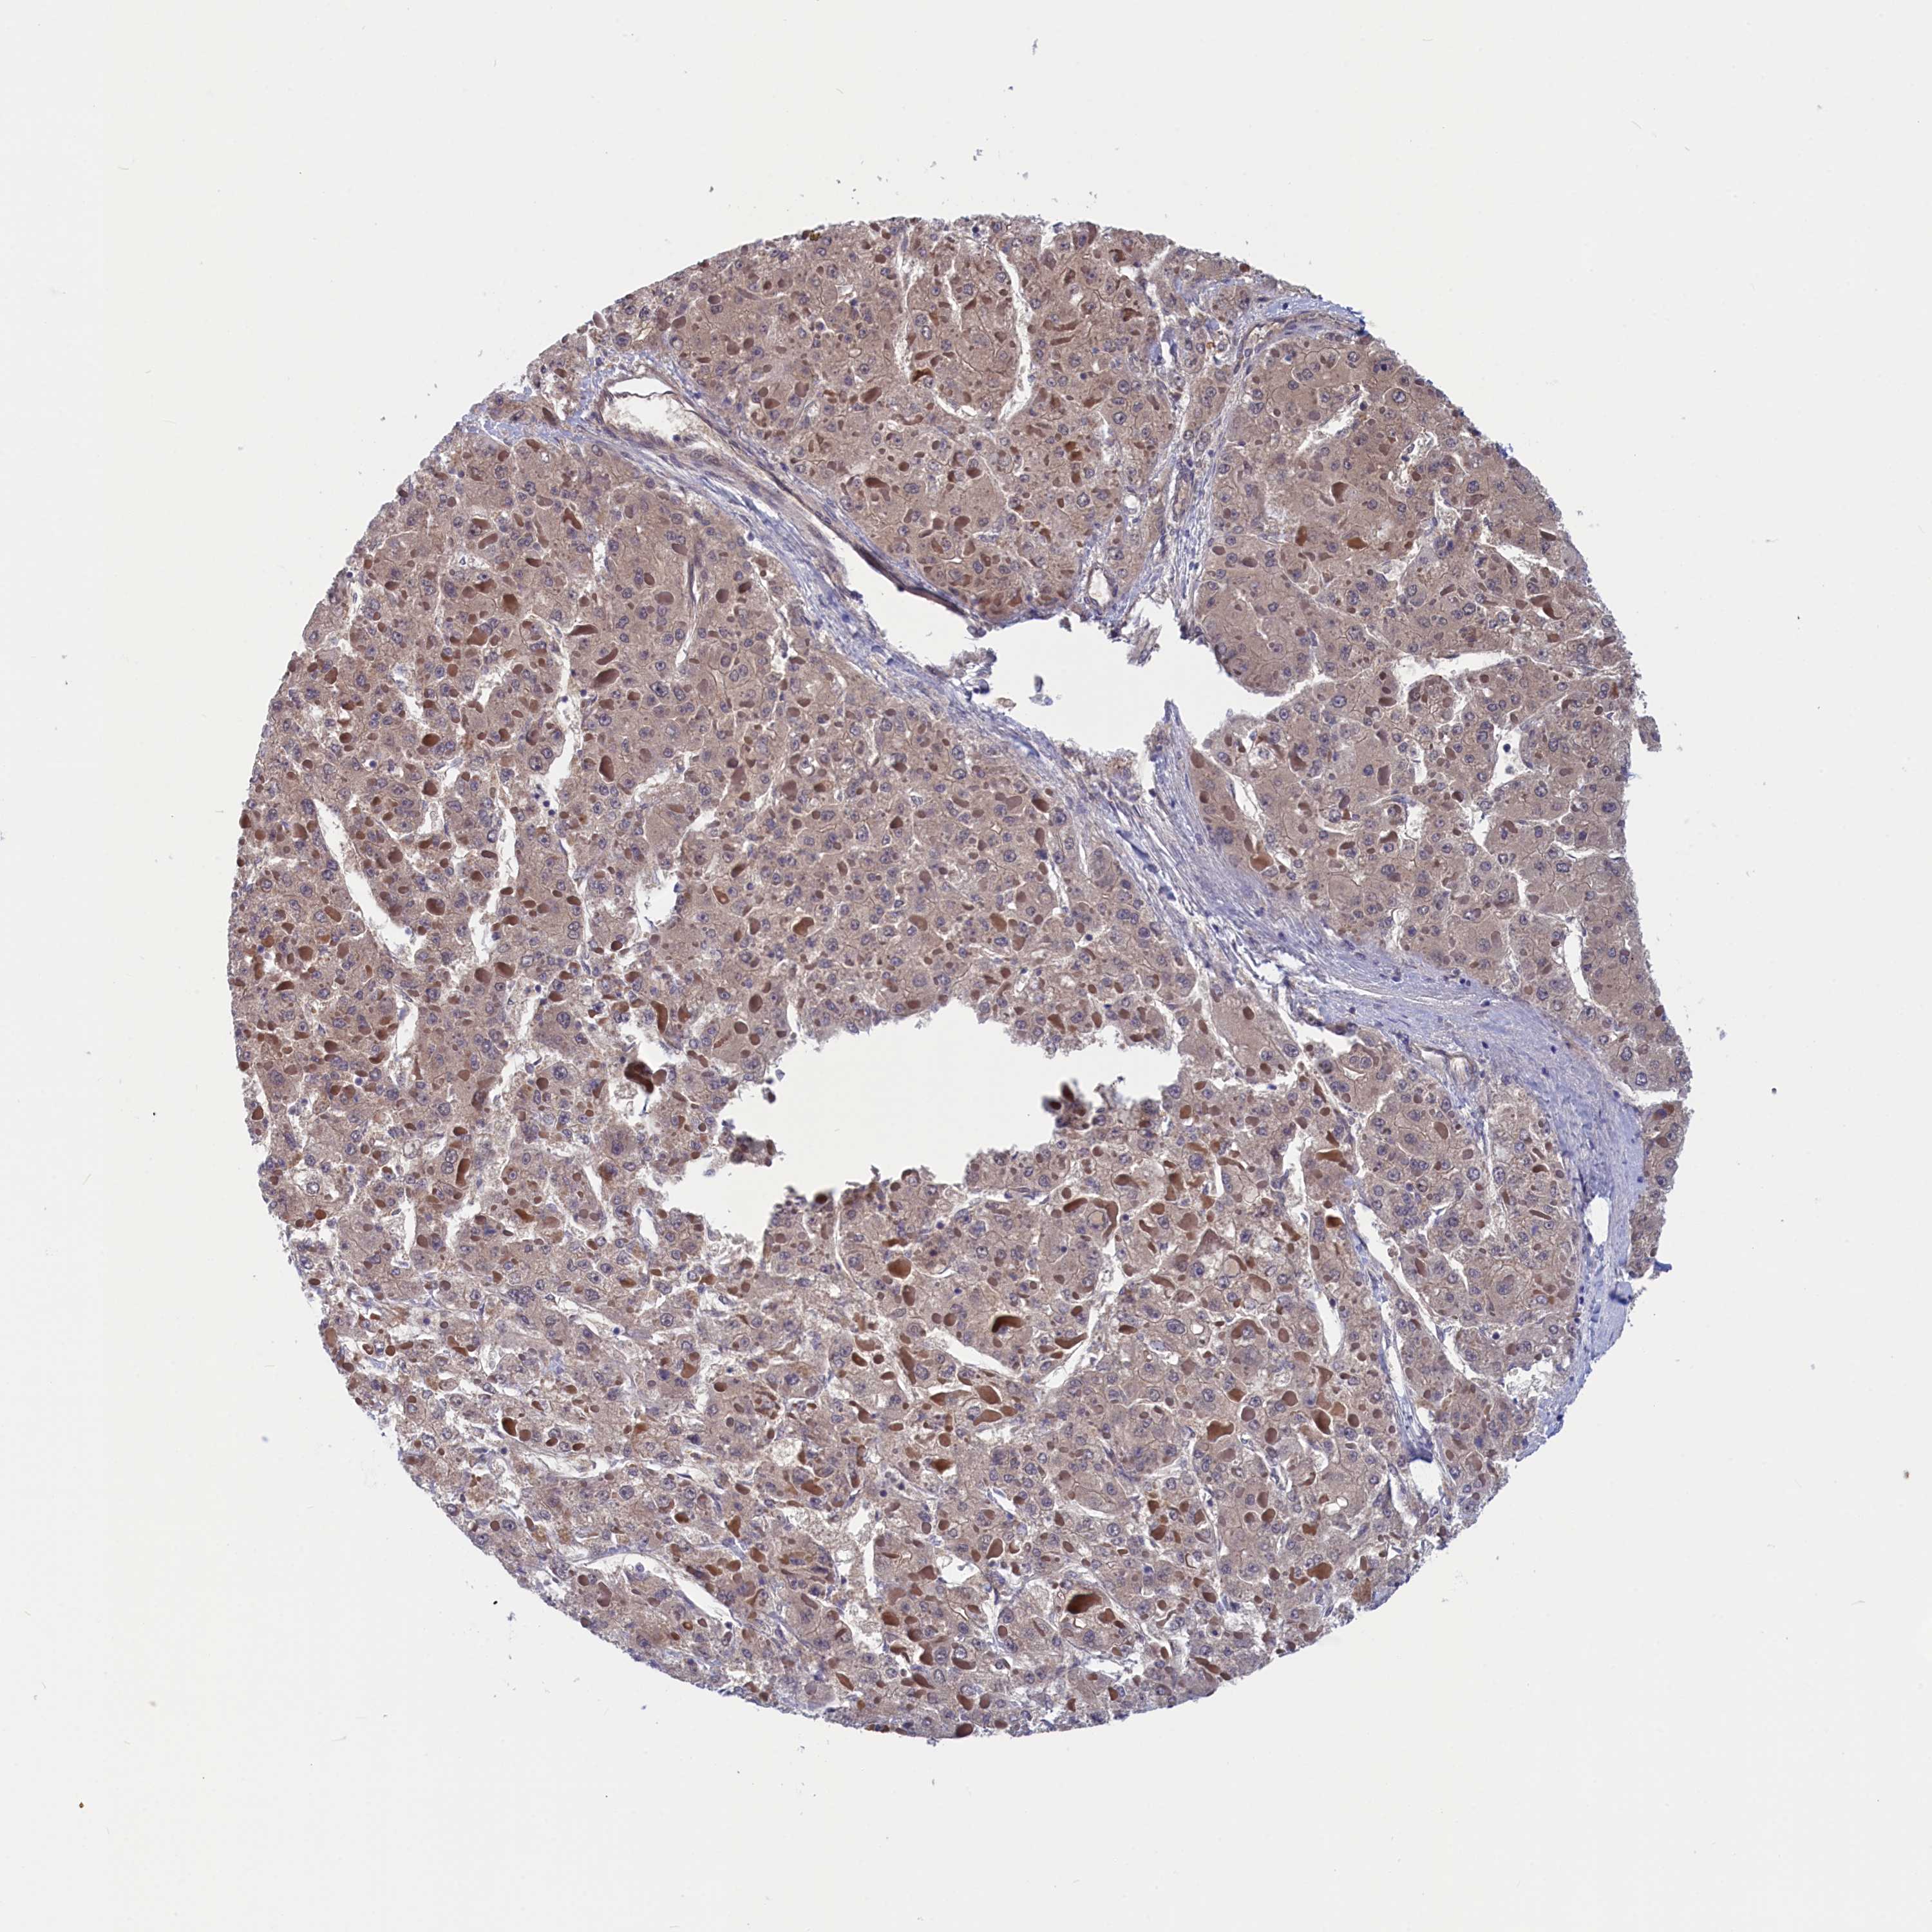

LIVER CANCER - Protein expressioni

A mouse-over function shows sample information and annotation data. Click on an image to view it in a full screen mode. Samples can be filtered based on level of antibody staining by selecting one or several of the following categories: high, medium, low and not detected. The assay and annotation is described here.

Note that samples used for immunohistochemistry by the Human Protein Atlas do not correspond to samples in the TCGA dataset.

Antibody stainingi

Antibody staining in the annotated cell types in the current human tissue is reported as not detected, low, medium, or high, based on conventional immunohistochemistry profiling in selected tissues. This score is based on the combination of the staining intensity and fraction of stained cells.

Each image is clickable and will lead to virtual microscopy that enables deeper exploration of all samples and also displays staining intensity scores, fraction scores and subcellular localization as well as patient and tissue information for each sample.

Antibody HPA042629

Antibody HPA042838

Staining

High

Medium

Low

Not detected

Intensity

Strong

Moderate

Weak

Negative

Quantity

>75%

75%-25%

<25%

None

Location

Nuclear

Cytoplasmic/membranous

Cytoplasmic/membranous,nuclear

Cholangiocarcinoma

Carcinoma, Hepatocellular, NOS